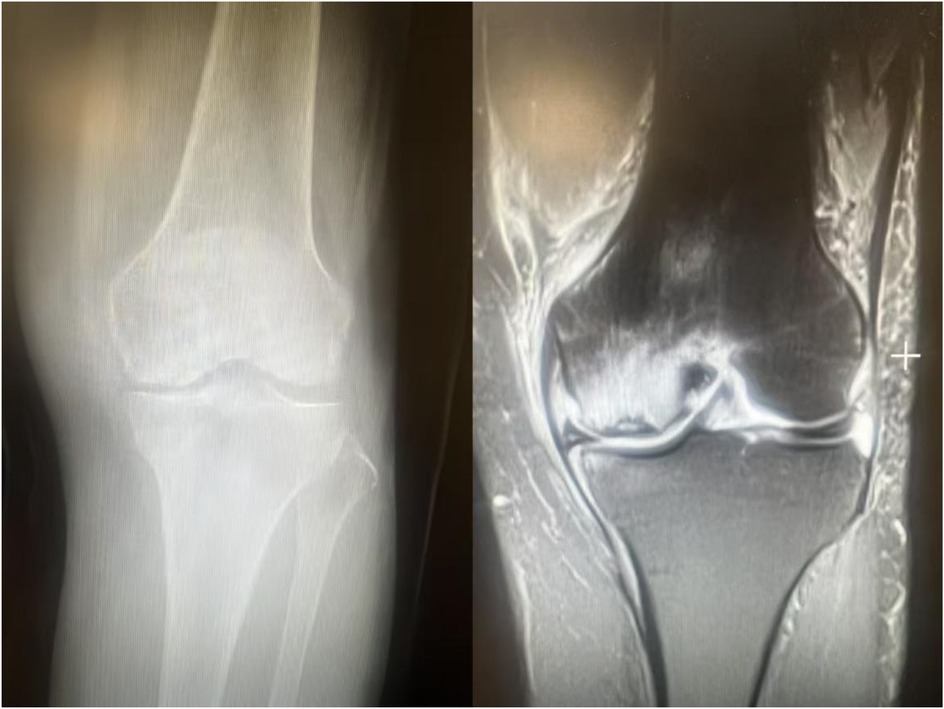

Subchondral insufficiency fracture of the knee (SIFK) was initially termed spontaneous osteonecrosis of the knee (SONK), a nomenclature first proposed by Ahlbäck et al. in 1968 (1). However, their study failed to provide histological evidence supporting osteonecrosis. It was not until 2000 that Yamamoto and Bulloug, through analysis of surgical bone specimens from SONK patients, demonstrated that the histological features were inconsistent with osteonecrosis (2). Subsequent studies further corroborated these findings, establishing that the pathological entity was fundamentally a subchondral fracture (3). Based on this evidence, Za P's team synthesized prior research to propose a new framework distinguishing SIFK from osteonecrosis of the knee (4) (Figure 1), advocating for the preferential use of “SIFK” over “SONK”. SIFK most commonly occurs in the medial femoral condyle of the knee (Figure 2), though involvement of the lateral condyle and tibial plateau has also been documented (5). The condition progresses rapidly, often leading to articular surface collapse and subsequent advanced SIFK. Epidemiological studies indicate a prevalence as high as 9.6% among elderly individuals aged 65 and older, with women affected 3–5 times more frequently than men (6). Additionally, the condition is increasingly observed in young adults engaged in excessive physical activity (7).